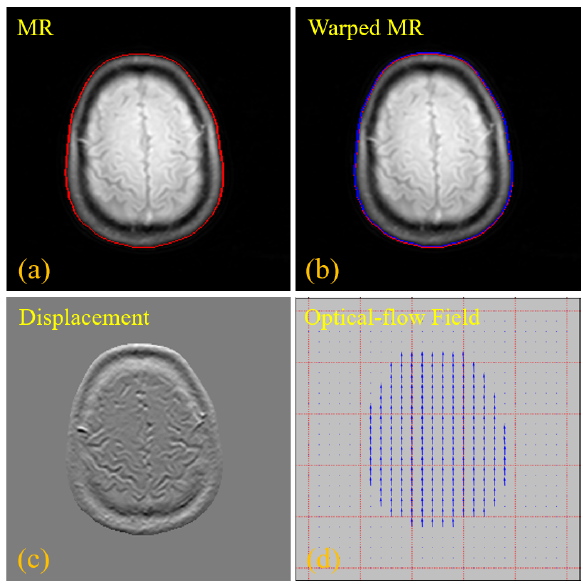

图2 基于光流配准的轮廓学习技术,(a)原始输入的MR 图像,红色曲线代表 MR图像的轮廓,(b)配准模块校正后的 MR 图像,蓝色曲线表示配准MR图像的轮廓,(c)配置变换前后的MR图像之间的像素强度差异,(d)稀疏光流场,显示配准预测网络的水平和垂直方向偏移量

由于PET/MR两种模态在纹理上存在显著性差异,直接顺利获得卷积学习这两种模态之间的对齐映射关系非常困难。由此,团队第一时间使用传统的图像腐蚀和膨胀技术来计算PET和MR图像的主要轮廓,然后再基于这些轮廓信息来构建光流的偏移量。基于轮廓学习的方法不仅简单有效,而且使得水平和垂直方向偏移量的学习也更加精准。